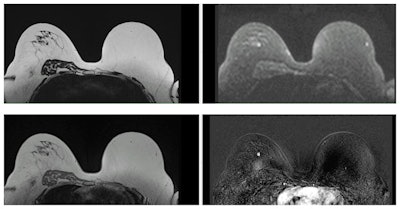

Examples of MR mammography images, courtesy of the University Hospital of Mannheim.The results showed that MRM was cost-effective. Based on current recommendations for economic evaluations the team defined a willingness to pay threshold (WTP) of $100,000 per quality-adjusted life years (QALYs). Therefore, an incremental cost-effectiveness ratio (ICER) below this WTP was assumed to be an indicator of cost-effectiveness.